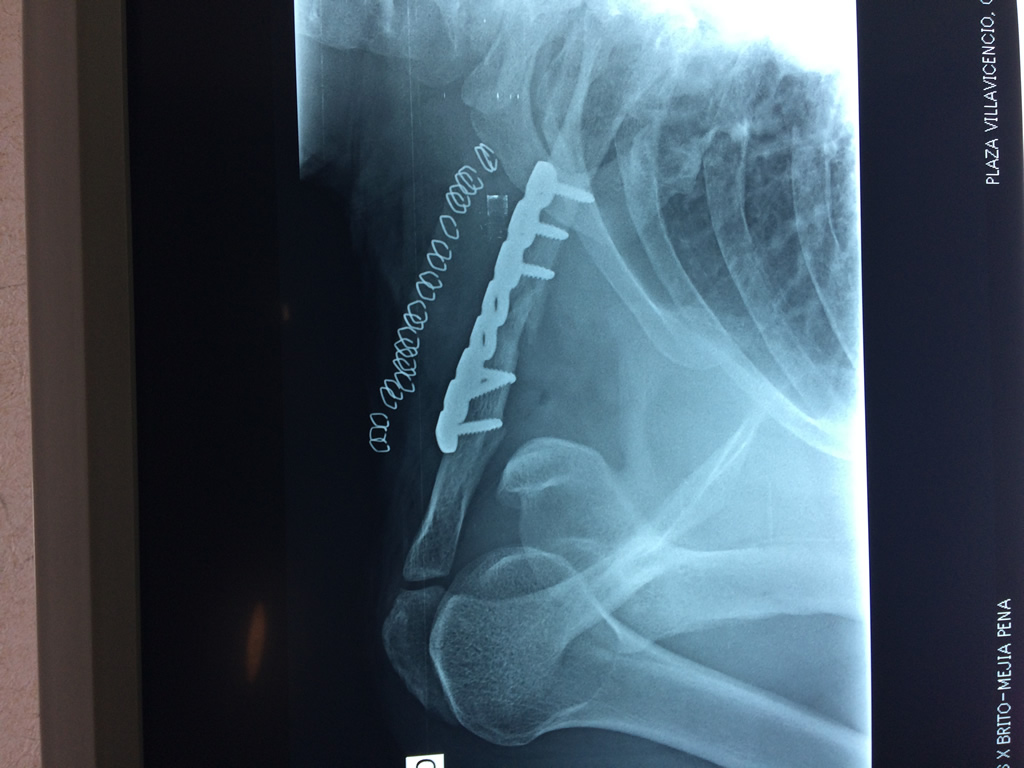

La clavícula es un hueso largo, con forma de "S" itálica, situado en la parte anterosuperior del tórax. Junto con la escápula forman la cintura escapular. Se puede palpar por toda su longitud y se extiende del esternón al acromion de la escápula, siguiendo una dirección oblicua lateral y posterior.

Se considera el único medio de unión entre el miembro superior y el tórax. A pesar de su aspecto, similar al de un hueso largo, posee una estructura semejante a la de un hueso plano, ya que carece de epífisis y de diáfisis, lo que la harían entrar dentro de la clasificación de hueso largo. Carece de un canal medular propiamente dicho.